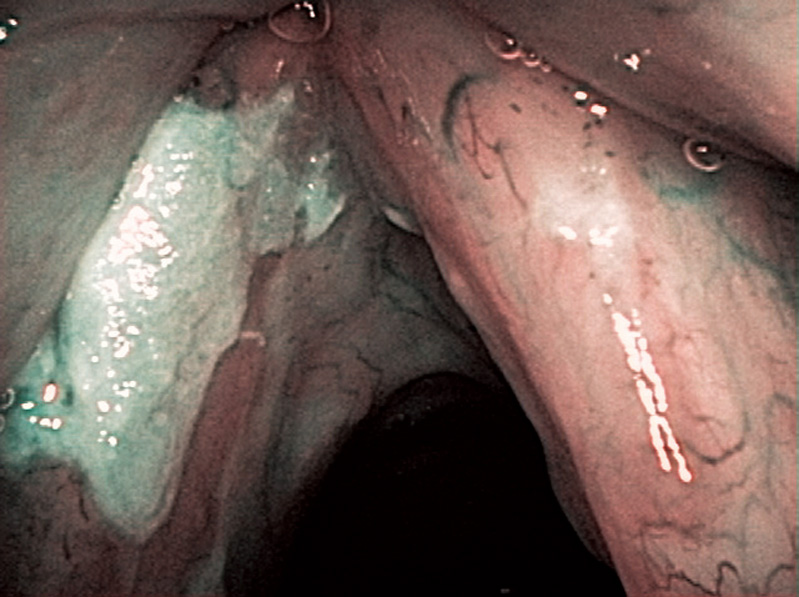

These are the peroral endoscopic findings observed under general anesthesia (through the laryngoscope). NBI was useful for the biopsy of the right vocal cord, because it was difficult to recognize the lesion in the white-light view. After the biopsy of the lesions, both vocal cords were vaporized with a YAG laser. The right vocal cord was pathologically diagnosed as an intraepithelial carcinoma and the left vocal cord was a dysplasia (low-grade).